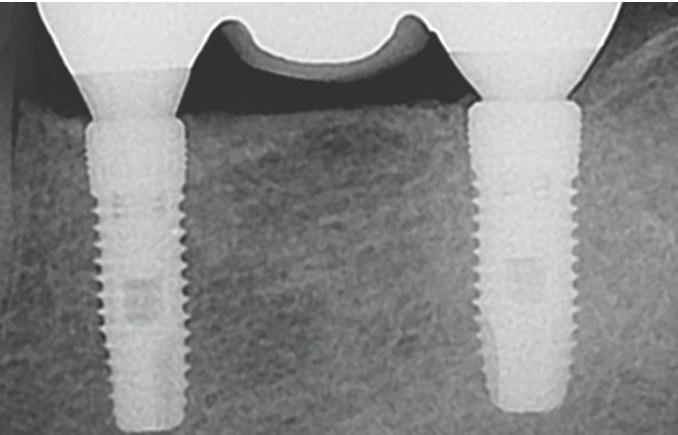

이미지 확대보기설립 이후 덴티움 임플란트는 우수한 품질을 바탕으로 2003년 유럽 CE 인증을 시작으로 2004년 미국 FDA를 포함하여 세계 여러 나라에서 의약품 제조 품질 기준(GMP)에 부합하는 제품의 안정성과 우수성을 인정받았다. 이후 유럽, 중국, 러시아, 중동, 아시아, 중남미 등 전 세계 70여 개국에 임플란트 제품을 수출하는 글로벌 기업으로 성장했다.

또 ‘Total Solution Provider & Self Development Manufacturer’를 모토로 2020년 글로벌 TOP3 진입을 위해 자체 연구개발(R&D)을 통한 차별화된 기술력을 확보했다. 그 결과 최고 품질의 치과용 임플란트와 생체 재료, 치과용 디지털 의료기기까지 아우르는 통합적인 임플란트 시스템을 구축하고 있다.

특히 덴티움의 핵심 동력인 덴티움 R&D Center는 안정성과 유효성 검증이 가능한 첨단 설비 시스템을 구축하여 세계 유수의 대학과 전문 연구 기관의 협력 하에 제품 개발과 연구를 활발히 진행하고 있다.